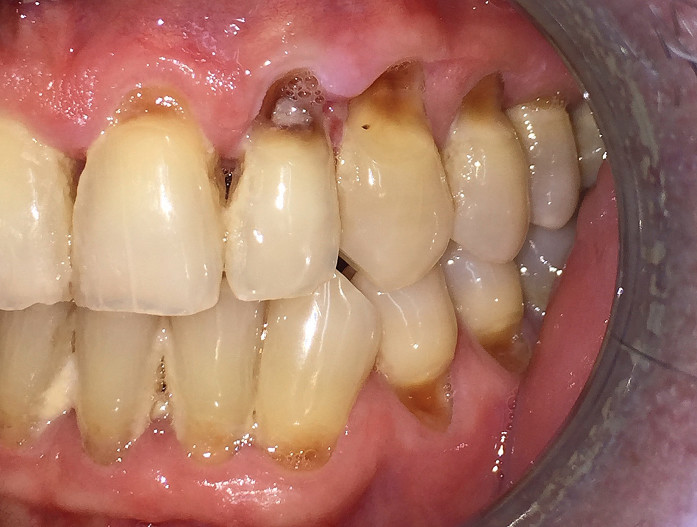

Wurzelkaries

Die Wurzelkaries ist stark assoziiert mit fortschreitendem Alter und gingivalen Rezessionen. Ihr Auftreten wird begünstigt durch eine ungenügende Belagentfernung, diätische Gewohnheiten und einen verminderten Speichelfluss.2 Kariöse Zahnhalsdefekte – besonders im Approximalbereich des Zahnhalses bzw. der Wurzeln – sind sehr schwierig zu restaurieren und bereiten dem Zahnarzt häufig große Probleme (Abb. 2a und b).